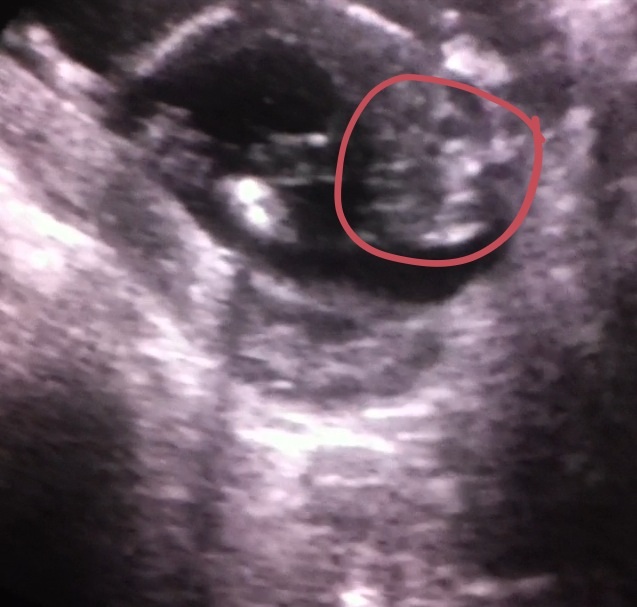

1st 2 pics were from 16 weeks scan everyone was unsure of those. ***NEW 3 pictures from 17 weeks scan

The first two images look like a boy. Congrats!

Thinking girl.